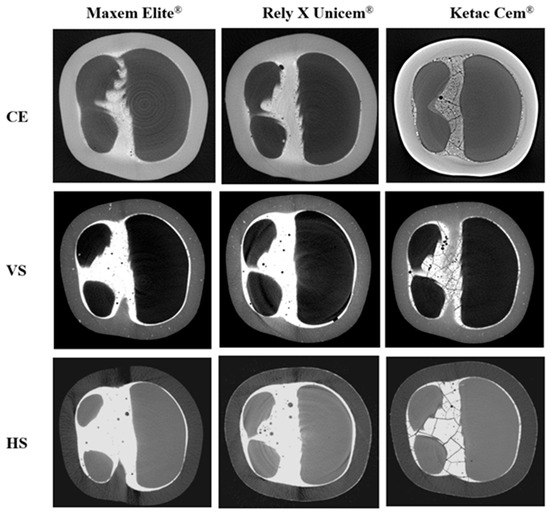

This in vitro study investigated the fracture resistance of three ceramic-reinforced polymer (CRP) crowns—Cerasmart® 270 (CE; milled), VarseoSmile Crown Plus® (VS; 3D-printed) and the newly developed Hassawat-01 (HS; 3D-printed)—luted with cements of different elastic moduli. The principal hypothesis was that neither [...] Read more.

This in vitro study investigated the fracture resistance of three ceramic-reinforced polymer (CRP) crowns—Cerasmart® 270 (CE; milled), VarseoSmile Crown Plus® (VS; 3D-printed) and the newly developed Hassawat-01 (HS; 3D-printed)—luted with cements of different elastic moduli. The principal hypothesis was that neither the CRP type nor the modulus of cement would significantly affect fracture resistance. Ninety-nine mandibular first molar resin dies were restored with 1 mm thick CE, VS, or HS crowns (n = 33 each) and luted with Maxcem Elite®, RelyX Unicem®, or Ketac Cem® (n = 11 per subgroup). Occlusal cement morphology was evaluated using Micro-CT. Fracture resistance was measured using a universal testing machine. Crowns luted with Maxcem or RelyX withstood forces >2000 N without visible failure. Ketac-luted crowns showed reduced fracture resistance. CE-Ketac fractured in 4 of 11 specimens. VS-Ketac exhibited cracks or complete fractures (1795.2 ± 156.7 N), whereas HS-Ketac showed only superficial cracking (1732.6 ± 127.3 N). CRP crowns luted with lower-modulus resin cements demonstrated superior fracture resistance compared with those luted with glass-ionomer. VS exhibited both cracking and occasional complete fractures, whereas HS exhibited only surface cracking. All materials withstood loads greater than typical masticatory forces, supporting HS as a promising alternative within the CRP. Full article

Show Figures

Figure 1